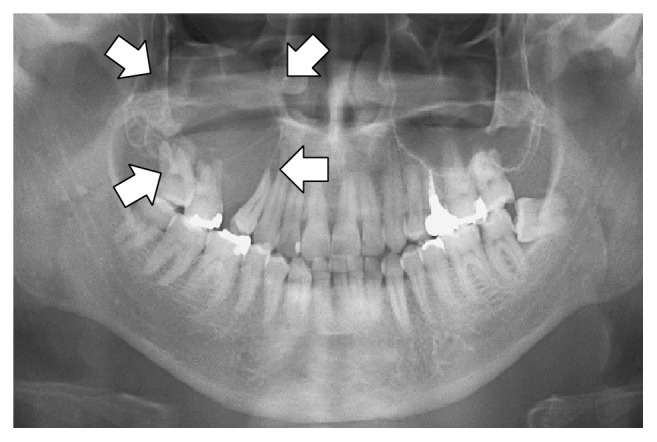

* **Llama 3.2 Vision** レントゲン撮影向けのファインチューニング: [ノートブック](https://colab.research.google.com/github/unslothai/notebooks/blob/main/nb/Llama3.2_\(11B\)-Vision.ipynb)\

X線、CTスキャン、超音波の解析を医療専門家がより速く行えるように支援するにはどうすればよいか。

視覚またはマルチモーダルモデルのファインチューニング用データセットは、標準的な質問と回答のペアに似ています [datasets ](https://unsloth.ai/docs/jp/meru/fine-tuning-llms-guide/datasets-guide)、しかし今回は画像入力も含まれます。例えば、 [Llama 3.2 Vision ノートブック](https://colab.research.google.com/github/unslothai/notebooks/blob/main/nb/Llama3.2_\(11B\)-Vision.ipynb#scrollTo=vITh0KVJ10qX) では放射線画像のケースを使用して、AIがX線、CTスキャン、超音波検査をより効率的に分析するのにどのように役立てるかを示しています。

ROCO放射線データセットのサンプリング版を使用します。データセットにアクセスできます [ここ](https://www.google.com/url?q=https%3A%2F%2Fhuggingface.co%2Fdatasets%2Funsloth%2FRadiology_mini)。データセットには医療状態や疾患を示すX線、CTスキャン、超音波画像が含まれており、各画像には専門家が記述したキャプションがあります。目標はVLMをファインチューニングして医療専門家にとって有用な分析ツールにすることです。

データセットを見て、最初の例が何を示しているか確認しましょう: